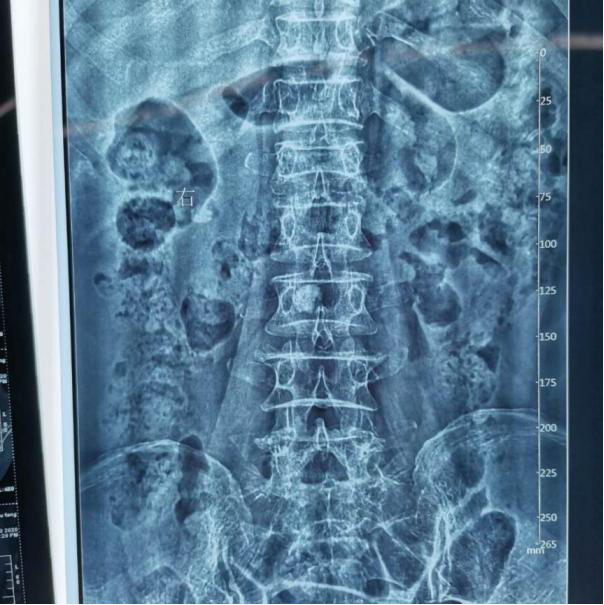

区三医院骨科成功开展首例经皮椎体后凸成形术

近日,我院骨科雷春副主任医师团队成功完成首例经皮椎体后凸成形术。术后患者疼痛明显消失,第二天即可下床行走,功能恢复满意,日常生活能力良好,术后3天出院。椎体形成术的成功开展,标志着我院骨科在微创治疗水平迈向新的台阶。

11月3日,赵婆婆因腰部受外伤,导致疼痛及活动受限入院,经专家组会诊,诊断为骨质疏松性腰1椎体压缩性骨折。考虑到腰椎骨折保守治疗需要长期卧床,易并发肺部感染、尿路感染、深静脉血栓等并发症。为尽快减轻患者疼痛,改善生活质量,骨科雷春副主任医师为赵婆婆制定了快速康复计划。11月19日,在手术室配合下雷春副主任医师、刘宗文副主任医师、徐海林医师共同完成了经皮椎体后凸成形术,手术历时1小时,术后患者疼痛即明显减轻,活动明显改善,术后第2天即可下床走动,术后功能恢复良好!

术前

术后